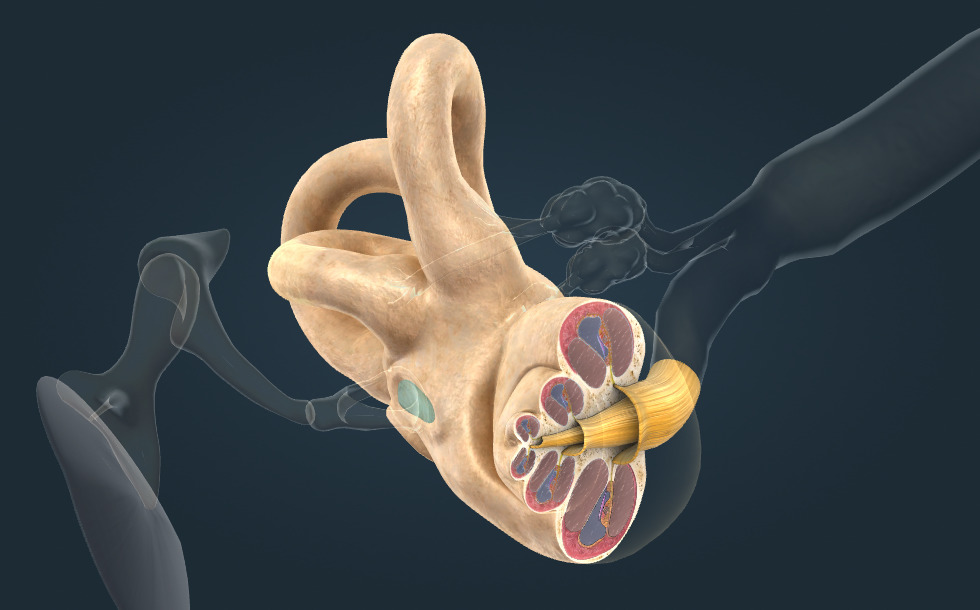

- ušní boltec - Zvukové vlny převádí do vnějšího zvukovodu. Skládá se především z chrupavky.

- vnější zvukovod - Zvukové vlny převádí k bubínku. Výstelka zvukovodu obsahuje mazove žlázy, které produkujú ušní maz, který ji chrání před poraněními a infekcemi. Nadměrný ušní maz může bránit průchodu zvuku do zvukovodu, což způsobuje dočasnou ztrátu sluchu.

- střední ucho - Začíná bubínkem, na němž jsou napojeny tři sluchové kůstky. S hltanem ho propojuje Eustachova trubice.

- vnitřní ucho - Má důležitou roli při rovnováze a slyšení.

- sluchový nerv - VIII. hlavový nerv, nesoucí signály z hlemýždě vnitřního ucha do mozku. Tento nerv také nese informaci zodpovědnou za vnímání rovnováhy, a proto je také nazýván sluchově rovnovážný nerv.

- ušní boltec - Zvukové vlny převádí do vnějšího zvukovodu. Skládá se především z chrupavky.

- vnější zvukovod - Zvukové vlny převádí k bubínku. Výstelka zvukovodu obsahuje mazove žlázy, které produkujú ušní maz, který ji chrání před poraněními a infekcemi. Nadměrný ušní maz může bránit průchodu zvuku do zvukovodu, což způsobuje dočasnou ztrátu sluchu.

- střední ucho - Začíná bubínkem, na němž jsou napojeny tři sluchové kůstky. S hltanem ho propojuje Eustachova trubice.

- vnitřní ucho - Má důležitou roli při rovnováze a slyšení.

- sluchový nerv - VIII. hlavový nerv, nesoucí signály z hlemýždě vnitřního ucha do mozku. Tento nerv také nese informaci zodpovědnou za vnímání rovnováhy, a proto je také nazýván sluchově rovnovážný nerv.

Sluchové kůstky

- ušní bubínek - Membrána, která odděluje vnější ucho od středního ucha. Vlivem zvukových vln začne vibrovat. Tato vibrace se přenáší na kůstky. V případě paracentézy se na bubínku provede malý řez, který umožní odtok hnisu ze zaníceného středního ucha.

- kladívko - Vnější ušní kůstka, přenáší vibrace z ušního bubínku na kovadlinku.

- kovadlinka - Centrální ušní kůstka, přenáší vibrace kladívka na třmínek.

- třmínek - Nejvnitřnější ušní kůstka, přenáší vibrace z kovadlinky do hlemýždě. Je to nejmenší kost lidského těla.

Hlemýžď

- 3 polokruhovité kanálky - Vnímají úhlové zrychlení hlavy. Když hlavu otočíme nebo nakloníme kterýmkoliv směrem, v receptorech polokruhovitých kanálů se vytvoří signál, který se přes axony sluchového nervu (sluchově rovnovážný nerv) přenese do mozku.

Zvuk je vibrací vzduchu, vnímáme ho ušima. Zdravé uši mohou vnímat zvukové vlny s frekvencí od 20 do 20 000 Hz. Stárnutím nebo vystavováním se neustálému hluku se škála frekvence zužuje.

Zvukové vlny vytvářejí signály ve vnitřním uchu, které jsou přenášeny sluchovým nervem a sluchovými drahami do sluchového centra mozkové kůry. Sluchový vjem se vytváří v mozkové kůře.

Zvukové vlny zachycuje ušní boltec a vede je do vnějšího zvukovodu. Zvuk rozvibruje bubínek, který uzavírá zvukovod.

Vibrace bubínku se přenášejí k hlemýždi pomocí kůstek, kladívka, kovadlinky a třmínku.

Spodek třmínku je přizpůsoben oválnému okénku hlemýždě. Bazilární membrána je umístěna uvnitř hlemýždě, vede podél špičky hlemýždě, kde se otočí a pokračuje v Reissnerově membráně. Membrána rozděluje hlemýždě na 3 dutiny: vestibulární, hlemýžďový a bubínkový kanál.